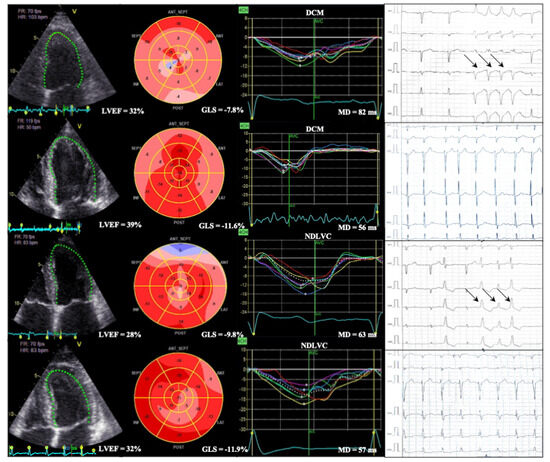

Mechanical Dispersion in Dilated and Non-Dilated Left Ventricular Cardiomyopathy: A New Frontier in Arrhythmic Risk Prediction

Background: Sudden cardiac death (SCD) is a major challenge in dilated (DCM) and non-dilated left ventricular cardiomyopathy (NDLVC). Current management strategies, based on left ventricular ejection fraction (LVEF), the presence or extent of myocardial scar, and selected high-risk genetic variants, are insufficient to [...] Read more.

Background: Sudden cardiac death (SCD) is a major challenge in dilated (DCM) and non-dilated left ventricular cardiomyopathy (NDLVC). Current management strategies, based on left ventricular ejection fraction (LVEF), the presence or extent of myocardial scar, and selected high-risk genetic variants, are insufficient to accurately identify patients at risk. Mechanical dispersion (MD), derived from speckle-tracking echocardiography, is a potential marker of arrhythmic risk that reflects variability in regional myocardial contraction timing. Aim: The purpose of this narrative review is to synthesize current evidence on the predictive role of MD for ventricular arrhythmias (VA) and SCD in DCM and NDLVC, with particular emphasis on its relationship to myocardial fibrosis (MF) and established echocardiographic markers. Results: Across prospective and retrospective cohorts of DCM patients, increased MD has consistently identified individuals at higher arrhythmic risk, often independently of LVEF and global longitudinal strain (GLS). Reported threshold values for risk prediction range from 50 ms to 90 ms, with hazard ratios confirming incremental prognostic accuracy. The relationship between MD and MF assessed by late gadolinium enhancement (LGE) on cardiac magnetic resonance (CMR) remains uncertain: some patients experience VA in the absence of LGE, while others display elevated MD despite no detectable focal MF, suggesting that additional mechanisms contribute to the arrhythmogenic substrate in DCM and NDLVC. Conclusions: MD may enhance SCD risk stratification in DCM and NDLVC by reflecting components of the arrhythmic substrate that are not detected by conventional markers. Full article